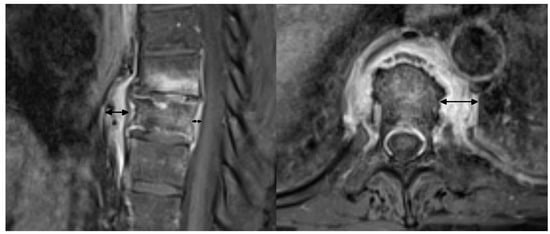

In adults, the main findings were BME, osteosclerosis, endplate irregularities, and a spectrum of ankylosing lesions. Similar to previous publications, the lesions were multilevel and contiguous [21,22,32,33]. Curvilinear/semicircular pattern of BME found in the majority of patients in the study by McGvuran and coworkers was less common in our material three patients); however, both BME and osteosclerosis overlapping BME on plain film/CT were definitely the most striking abnormalities (Figure 4) [22]. We also observed a long persistence of BME that was present through the whole length of follow up, even in patients followed for more than 10 years. On MRI, contrast enhancement was observed in the areas of BME, but also in the linear fashion along the endplates and frequently in the non-ankylosed costovertebral and facet joints. Paraspinal soft tissue involvement was observed in 10 out of 12 patients subjected to MRI (83%), more often than in previous publications [22,34]. In agreement with previous reports, most of the intervertebral discs showed decreased T2 signal corresponding to degeneration rather than the high signal seen in discitis [22]. Vertebral deformities were limited to anterior wedging, most pronounced at the apex of thoracic kyphosis. Ankylosing lesions were prevalent and, as previously reported, showed a progressive character on follow up [35,36]. Anterior bony bridging resembling this observed in diffuse idiopathic skeletal hyperostosis (DISH) was accompanied by intervertebral fusion and facet joint ankylosis. Contrary to previous reports, we have not observed the resolution of hyperostosis once ankylosis was complete [36].

Figure 4.

Imaging findings of the thoracic spine involvement in a 65-year-old patient with SAPHO syndrome. CT (A) shows multilevel, contiguous vertebral osteosclerosis, endplate erosions, and early syndesmophyte formation. MRI (B) shows diffuse and propagating patterns of BME and mild prevertebral soft tissue inflammation.